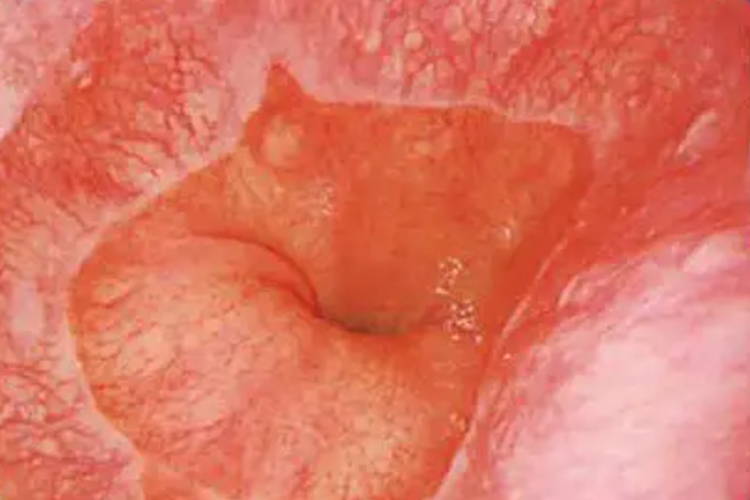

BARRETT食管是指食管下段的复层鳞状上皮被单层柱状上皮所替代的病理状态的食管,胃镜下可看到齿状线,以及胃和食管的交界线。

BARRETT食管在胃镜下可以看到两个分界线,一是齿状线,为食管鳞状上皮和胃柱状上皮交界线,胃镜表现为两种色调的交界线,呈齿状,边缘不齐。二是食管-胃交界,为食管腔与胃纵行皱襞交界处。